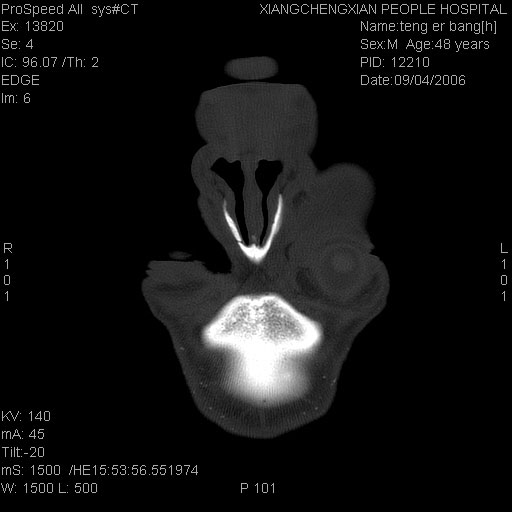

ct:平扫+冠扫:双侧鼻骨对比,冠扫s6#示右侧鼻骨尖部可见线状低密度影,边缘光滑,并见硬化.软组织未见肿胀.

诊断意见:鼻额缝(鼻骨与上颌骨额突缝),但个别同志认为是骨折.因此请同行们会诊.多谢了!

正常鼻颌缝。软组织无肿胀。鼻腔无积液积血。鼻骨光滑规整无中断。均不支持骨折。

正常鼻颌缝。软组织无肿胀。鼻腔无积液积血。鼻骨光滑规整双侧对称。均不支持骨折。